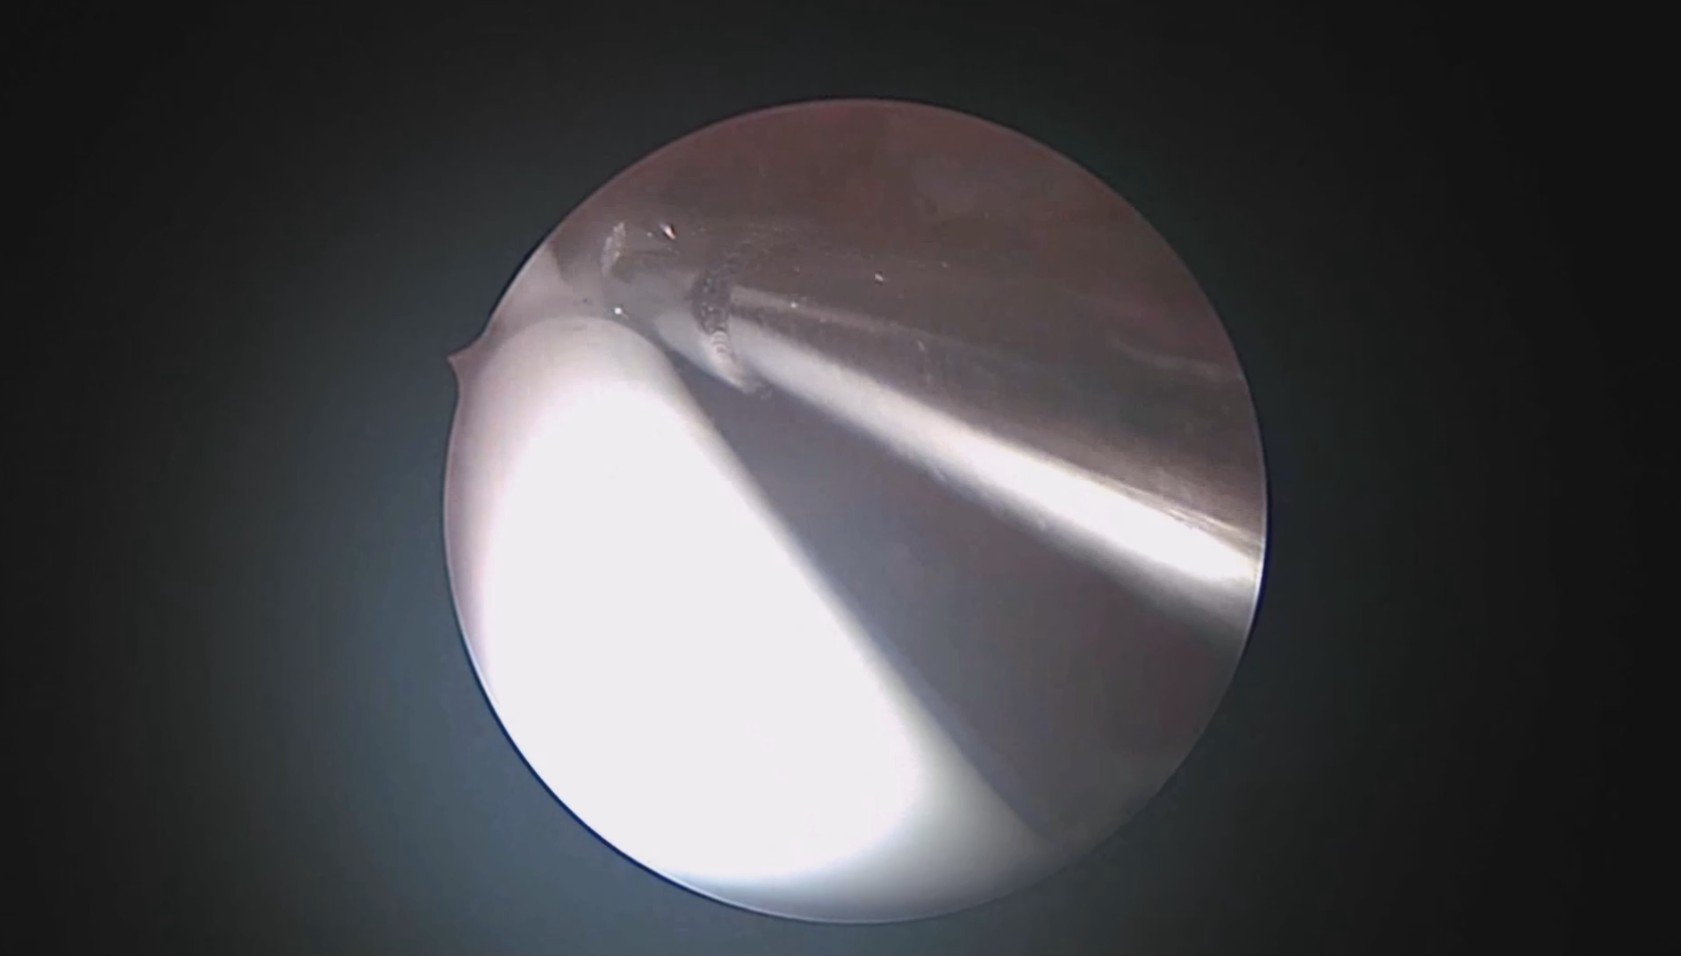

患者41岁,G4P2,顺产2次。因异常子宫出血于2023年12月在外院行宫腔镜检查,取内膜病检为增生晚期及分泌早期宫内膜组织,另见宫内膜息肉,术后药物治疗效果不佳,月经周期不规律。本次阴道不规则流血10+天,量多就诊。宫腔镜下尝试线结扣宫底锚定曼月乐,将结推人宫底肌层很困难,最后采用不锈钢挂钩固定。用曼月乐尾丝连接环与不锈钢挂钩,将挂钩插入宫底肌层,异物钳原位固定曼月乐,退出宫腔镜,结束手术。术后患者未回院复查节育环位置。